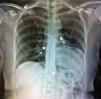

A 46-year-old woman was referred to our department with symptoms of palpitations and atypical chest pain. Clinical examination found a palpable apical impulse on the midaxillary line. Electrocardiogram revealed sinus rhythm with a heart rate of 90 bpm, left anterior fascicular block and incomplete right bundle branch block. Chest X-ray (Figure 1) revealed levoposition and a “teardrop” appearance of the heart, superimposition of the right cardiac border over the spine, a prominent main pulmonary artery and a translucent area between the heart and the diaphragm.